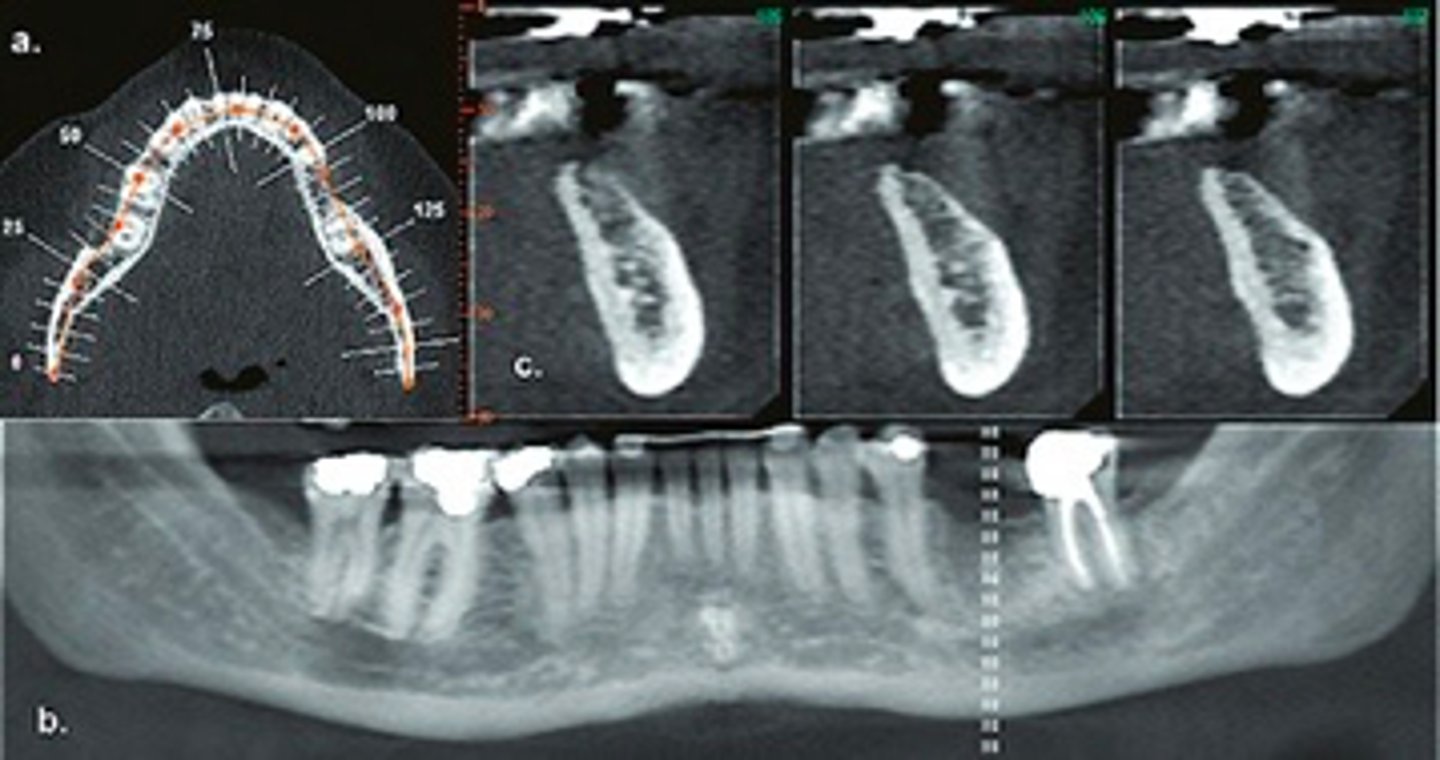

CBCT

ID the type of Imaging modality:

- Pano

- CT

- CBCT

- MRI

- Technetium 99 bone scans

- PET